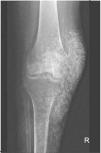

Medicina en imágenes

Mujer de 47 años con úlceras recidivantes y placas induradas en miembros inferiores